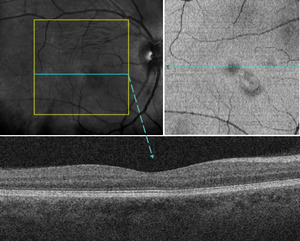

Optical coherence tomography angiography (RTVue XR Avanti, Optovue Inc.) with 6 × 6-mm angiograms was acquired. System software restricted quantified analysis of the vessel density below the superficial retinal vascular slab. Qualitative analysis of the vascular slabs in the right eye showed no appreciable decrease in vessel density within the superficial, deep, or choriocapillaris slabs (Figure 4). The outer retina slab is inherently avascular and revealed an area of hyporeflectivity from projection artifact (Figure 4). Standard fluorescein and indocyanine green angiography were not ordered because of limited diagnostic utility for acute macular neuroretinopathy.

Optical coherence tomography angiography is a noninvasive imaging technique used to map retinal and choroidal vascular networks via red blood cell motion detection. Recent reviews using this imaging modality have enhanced our acute macular neuroretinopathy pathophysiology understanding.6,10,33 Focal flow voids may be observed within the deep capillary plexus and choriocapillaris corresponding to acute macular neuroretinopathy lesions.6,7,10,33 Decreases in global vessel density have been identified only within the choriocapillaris.10 This patient demonstrated no discernible qualitative changes in the superficial, deep, or choriocapillaris vascular slabs, albeit with a lower resolution 6 × 6-mm angiogram acquired 5 months after initial symptoms onset.